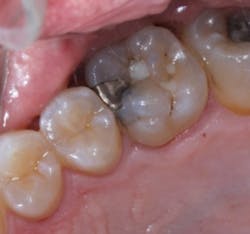

Upon removal of the amalgam there was a large area of caries along the buccal margin, distal margin and extending on to the gingival floor of the preparation. The buccal caries had begun to undermine the mesio-buccal cusp. If this had not been detected, the patient, at a minimum, would have fractured the buccal cusp.

Figure 5 The amalgam restoration removed showing caries along the gingival seat and the buccal and lingual walls of the preparation